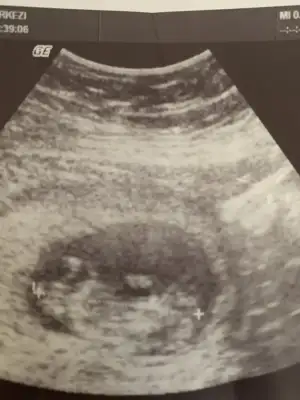

benimkini de görmediniz sanırım.6+2 karından ultrasonmerhaba.bi tahminde benim için bulunabilirmisiniz acaba :)

bu olur mu?6+2 karındanfotoğrafı yakınlaştırmadan çekip atabilir misiniz

paşa gibibu olur mu?6+2 karından